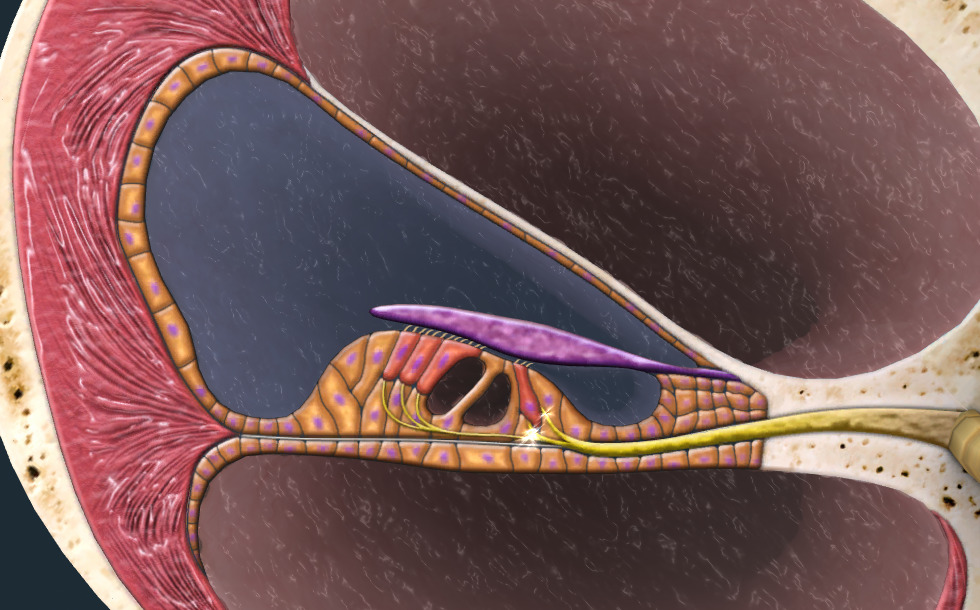

- vestibulární kanál - Třmínek rozvibruje tekutinu (perilymfu), která vyplňuje vestibulární kanál. Vibrace tekutiny se šíří směrem ke špičce hlemýždě.

- hlemýžďový kanál - Shora je oddělen Reissnerovou membránou, a zespodu bazilární membránou. Je naplněn tekutinou.

- bubínkový kanál - Je naplněn tekutinou (perilymfa). Vibrace v tomto kanálu se šíří od špičky směrem k spodní části hlemýždě.

Cortiho orgán

- vláskové buňky - Když se vibrace pohlcují bazilární a tektoriální membrána se vzájemně pohnou. Tektoriální membrána tlačí na chlupy vláskových buněk Cortiho orgánu, ohýbá je a tím generuje signál v buňkách. Trvalé působení hluku může způsobit zničení vlasových buněk, což vede k trvalé ztrátě sluchu. To je důvod, proč je důležité, adekvátní ochrana proti hluku na pracovišti.

- tektoriální membrána - Při pohlcení vibrace se bazilární a tektoriální membrána vzájemně pohnou. Tektoriální membrána se přitlačí k vláskovým buňkám Cortiho orgánu a ohne je, co ve vláskových buňkách vytvoří signál.

- bazilární membrána - Bazilární membrána pohlcuje vibrace šířící se v tekutině hlemýždě a začne vibrovat. Proto se bazilární a tektoriální membrána vzájemně pohnou.

- nervová vlákna

Spodek třmínku je přizpůsoben oválnému okénku hlemýždě. Bazilární membrána je umístěna uvnitř hlemýždě, vede podél špičky hlemýždě, kde se otočí a pokračuje v Reissnerově membráně. Membrána rozděluje hlemýždě na 3 dutiny: vestibulární, hlemýžďový a bubínkový kanál.

Hlemýžď je naplněn tekutinou, která se rozkmitá pomocí třmínku. Vibrace s vyšší frekvencí, které vznikají při vyšším zvuku, jsou pohlceny na spodku hlemýždě a rozvibrují bazilární membránu. Vibrace s nižší frekvencí vytvářejí hluboké zvuky a rozvibrují bazilární membránu na vrchu hlemýždě. Když dojde k pohlcení vibrace, vytváří se elektrický signál, který je přenášen do mozku. Vznik elektrického signálu, který je kódován na místě pohlcení, se nazývá tonotopie.

Elektrické signály jsou generovány v Cortiho orgánu. Vlivem vibrací, které se šíří v hlemýždi, se tektoriální membrána přitlačí k vláskovým buňkám na bazilární membráně, vlásky se ohnou a vytvoří se signál. Cortiho orgán mění vibrace na elektrické signály, které jsou prostřednictvím vláken sluchového nervu přenášeny do mozku a pak přes sluchové dráhy do mozkové kůry. Sluchový vjem je produkován v mozkové kůře.